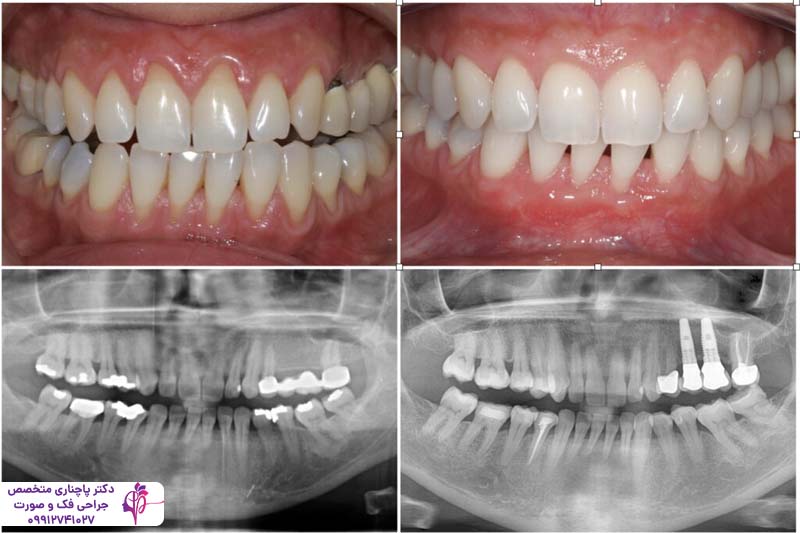

درمان بیماریهای لثه قبل از ایمپلنت یکی از مهمترین مراحلی است که باید انجام شود. بیماریهای لثه در صورت عدم درمان میتوانند تاثیر مستقیم روی موفقیت کاشت ایمپلنت داشته باشند. در دنیای دندانپزشکی مدرن ایمپلنت دندان به عنوان یکی از پیشرفتهترین روشها برای جایگزینی دندانهای از دست رفته به شمار میرود. این روش هم ظاهر طبیعی را به دندانها برمیگرداند هم عملکرد فک را هنگام جویدن و صحبت کردن بهبود میبخشد. اما موفقیت کاشت ایمپلنت به عوامل مختلفی بستگی دارد و مهمترین آنها سلامت لثههاست. درمان بیماریهای لثه قبل از ایمپلنت اهمیت زیادی دارد چون وجود هر گونه عفونت یا التهاب در لثه میتواند باعث شکست کاشت ایمپلنت شود.

لثههای سالم پایه و اساس موفقیت عمل کاشت ایمپلنت هستند. پایههای تیتانیومی ایمپلنت که به صورت مستقیم داخل فک بیمار کاشته میشوند برای تثبیت نیاز به یک بستر محکم دارند و وجود این بستر محکم به سلامت بافت لثه و استخوان فک وابسته است. اگر لثهها سالم نباشند احتمال بروز عفونت و در نتیجه ادغام نشدن پایه ایمپلنت با استخوان فک وجود دارد. درمان بیماریهای لثه قبل از ایمپلنت تضمین میکند که هیچ باکتری و عفونت مضری در محیط دهان وجود ندارد و در نتیجه ریسک شکست ایمپلنت هم کم میشود. ایمپلنتهایی که در لثههای سالم قرار میگیرند نرخ موفقیتی بیشتر از 95 درصد دارند اما در مواردی که ایمپلنت با وجود بیماریهای لثه انجام میشود این نرخ به شکل قابل توجهی کم میشود. حفظ ساختار استخوان فک به داشتن لثه سالم گره خورده و این موضوع برای محکم شدن ایمپلنت در جای خود اهمیت زیادی دارد.

درمان بیماریهای لثه قبل از ایمپلنت معمولا در چند مرحله انجام میشود. در ابتدا دندانپزشک لثه بیمار را معاینه میکند و به کمک عکسبرداری عمق عفونت و شدت بیماری را تشخیص میدهد. در مرحله بعد به کمک ابزارهای اولتراسونیک پلاک و جرم را بدون آسیب به بافتهای سالم اطراف برمیدارد. پس از این کار بیمار باید بهداشت دهان و دندان را جدیتر رعایت کند و حتما از دهانشویههای ضدباکتری هم استفاده کند. برای موارد پیشرفتهتر ممکن است نیاز به جارحی باشد تا بافتهای عفونی کاملا برداشته شوند و لثه ترمیم شود. پس از طی شدن روند درمان بیمار باید به صورت منظم برای بررسی سلامت لثهها به دندانپزشک مراجعه کند.

در نهایت، درمان بیماری های لثه قبل از ایمپلنت کلیدی برای دستیابی به نتایج موفق و پایدار است. با درک اهمیت لثه سالم، علل و علائم بیماری، و روشهای درمان، بیماران میتوانند اقدام مناسب را انجام دهند و سلامت عمومی دهان و دندان خود را تضمین کنند. علاوه بر این داشتن یک لثه سالم و استخوان متراکم کلید موفقیت کاشت ایمپلنت است.